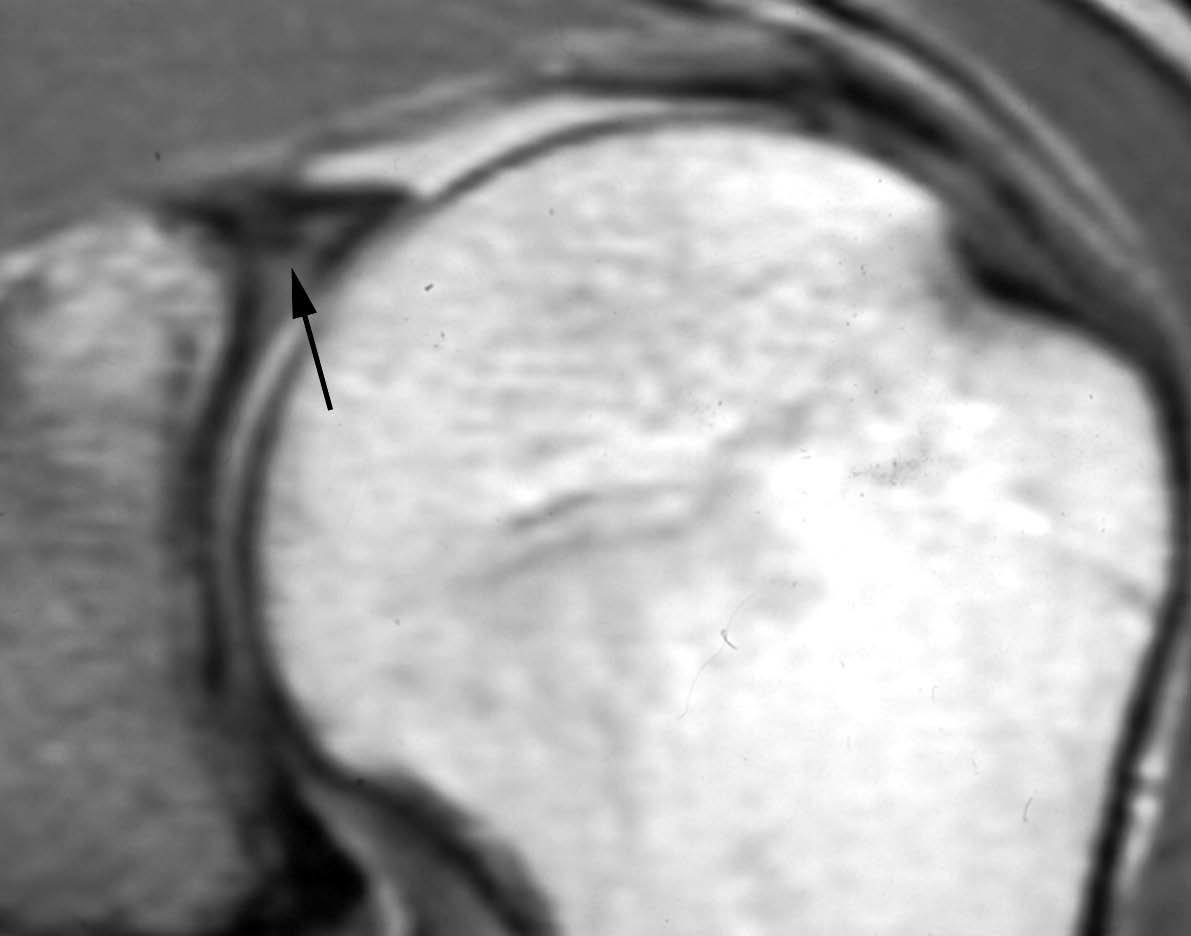

Fig. 1.--Foramen sublabial. Artrorresonancia T1 axial (A) y sagital oblicua (B) muestran el foramen sublabial (cabeza de flecha en A y flecha corta en B). Esta variante de la normalidad se encuentra entre la una y las tres, considerando la cavidad glenoidea como la esfera del reloj. Nótese el ligamento glomerohumeral medio (LGHM) (flecha larga en A) y el labio glenoideo (flecha larga en B).

Fig. 2.--Receso sublabial. Artrorresonancia T1 coronal oblicua que muestra un receso profundo sublabial. Nótese la orientación de esta variante hacia la cabeza del paciente (flecha).